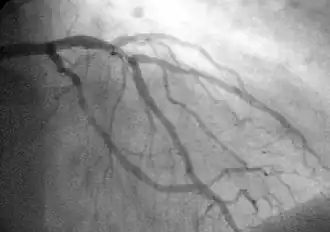

Coronary catheterization is one of the several cardiology diagnostic tests and procedures. Specifically, through the injection of a liquid radiocontrast agent and illumination with X-rays,[1] angiocardiography allows the recognition of occlusion, stenosis, restenosis, thrombosis or aneurysmal enlargement of the coronary artery lumens; heart chamber size; heart muscle contraction performance; and some aspects of heart valve function. Important internal heart and lung blood pressures, not measurable from outside the body, can be accurately measured during the test. The relevant problems that the test deals with most commonly occur as a result of advanced atherosclerosis – atheroma activity within the wall of the coronary arteries. Less frequently, valvular, heart muscle, or arrhythmia issues are the primary focus of the test.

During coronary catheterization (often referred to as a "cath" or "cardiac cath" by physicians), blood pressures are recorded and fluoroscopy (X-ray motion picture) shadow-grams of the blood inside the coronary arteries are recorded. In order to create the X-ray pictures, a physician guides a small tube-like device called a catheter, typically ~2.0 mm (6-French) in diameter, through the large arteries of the body until the tip is just within the opening of one of the coronary arteries. By design, the catheter is smaller than the lumen of the artery it is placed in; internal (intra-arterial) blood pressures are monitored through the catheter to verify that the catheter does not block blood flow (as indicated by "dampening" of the blood pressure).

The catheter is itself designed to be radiodense for visibility and it allows a clear, watery, blood compatible radiocontrast agent, commonly called an X-ray dye, to be selectively injected and mixed with the blood flowing within the artery. Typically 3–8 cc of the radiocontrast agent is injected for each image to make the blood flow visible for about 3–5 seconds as the radiocontrast agent is rapidly washed away into the coronary capillaries and then coronary veins. Without the X-ray dye injection, the blood and surrounding heart tissues appear, on X-ray, as only a mildly-shape-changing, otherwise uniform water density mass; no details of the blood and internal organ structure are discernible. The radiocontrast within the blood allows visualization of the blood flow within the arteries or heart chambers, depending on where it is injected.

If atheroma, or clots, are protruding into the lumen, producing narrowing, the narrowing may be seen instead as increased haziness within the X-ray shadow images of the blood/dye column within that portion of the artery; this is as compared to adjacent, presumed healthier, less stenotic areas.